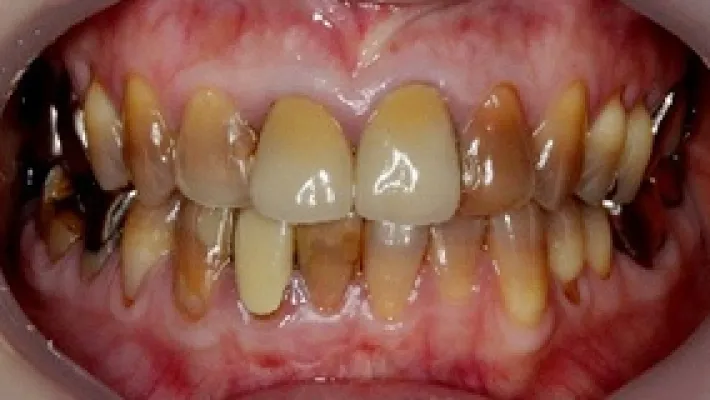

Case2. 上前歯8本 ラミネートベニア + ホワイトニング

施術前

施術後

削らないラミネートベニアでテトラサイクリン歯(茶色系グレー系の歯)の色を改善した症例です。

事前にホワイトニングを行い、ご自身の歯の色をできるだけ改善してからラミネートベニアを行いました。

ラミネートベニアに少し透明感を出すことで、周りの歯になじむ自然な仕上がりになりました。

*テトラサイクリン歯の色調には個人差があります。グレー色が濃い方、帯状の模様が強い方は事前にホワイトニングを行い、歯の色をできるだけキレイにしてからラミネートベニアを行うようにしています。

*テトラサイクリン歯でも不透明なベニアを選択すれば真っ白くすることができます。この症例では、あえて少し透明なベニアで歯の色が透けることで自然に調和するようにしています。